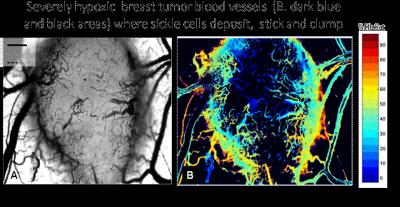

The mutation that causes sickle cell anemia changes the shape of red blood cells and makes them less efficient at transporting oxygen through the body. When there is little oxygen available in the environment (hypoxia), these sickle cells clump together and block blood vessels, eventually rupturing and damaging the blood vessel and surrounding cells. This is traumatic for those that suffer from the disease, but in this new research, scientists have harnessed this phenomenon to target certain tumors.

Hypoxia is also present in many solid tumors and causes resistance to chemotherapy and radiotherapy. Here, the researchers combined sickled blood cells with a molecule that can release large amounts of oxygen, and injected the cells into mice with severely hypoxic tumors. The sickled cells clumped up within the tumor blood vessels within minutes of injection, blocking tumor blood supply. As they ruptured, the oxygen-releasing molecule they carried also killed a significant proportion of tumor cells and blood vessels. Normal red blood moved freely through the tumors without clumping and did not kill the tumor cells.

Terman explains, "Sickle cells, unlike normal red blood cells, stick like Velcro to tumor blood vessels where they cluster and shut down the blood supply of oxygen deprived tumors. Once clumped within the tumor, the sickle cells rupture releasing toxic residues that promote tumor cell death."